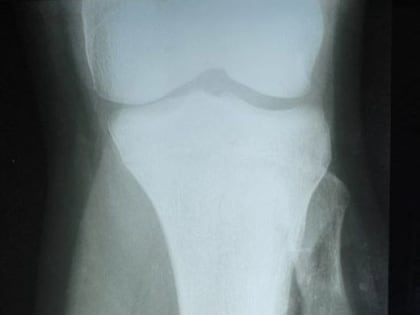

Донецкие врачи удалили подростку объемную опухоль кости14-летний подросток поступил в Республиканский травматологический центр (РТЦ) Минздрава ДНР с диагнозом «остеохондрома большеберцовой кости»